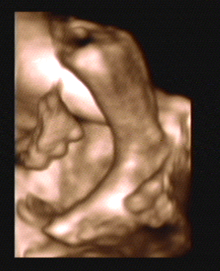

3D/4D SONOGRAPHY 18-24 WEEKS

- Normal Sonography is 2 dimensional. In 3 dimensional Sonography the information is obtained simultaneously in 3 planes (X, Y & Z).

- Highly sophisticated software reconstructs this information into a distinct 3D image.

- From a continuous 3D acquisition you get a live action view. It is known as 4D where 4th dimension is time.

- Improved identification of suspected or detected anomalies.

- More accurate identification of the extent & size of anomalies.